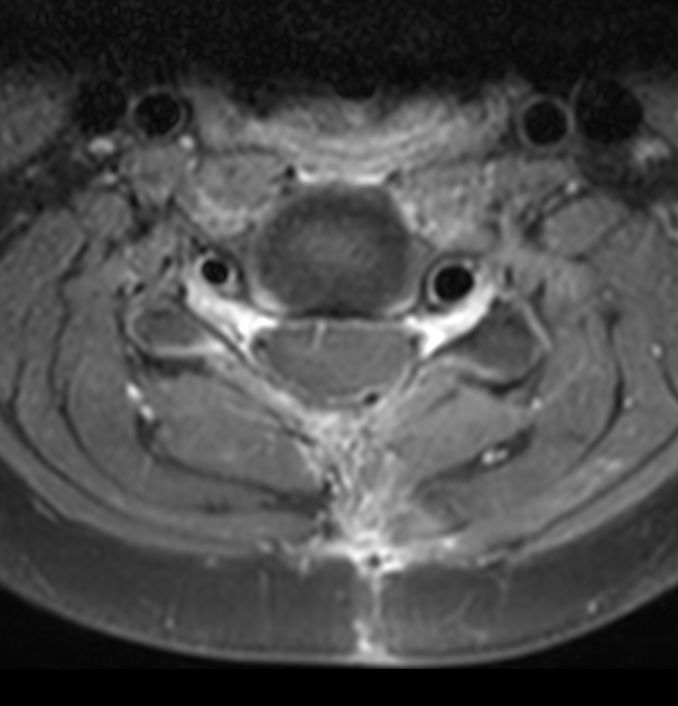

Axial 3D T2w TSE DRIVE